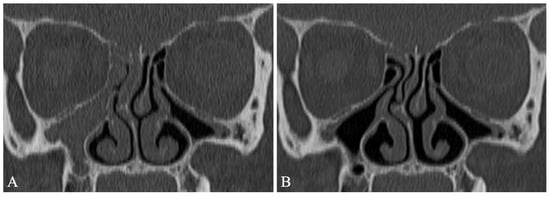

- Beswick, D.M.; Humphries, S.M.; Balkissoon, C.D.; Strand, M.; Vladar, E.K.; Lynch, D.A.; Taylor-Cousar, J.L. Impact of Cystic Fibrosis Transmembrane Conductance Regulator Therapy on Chronic Rhinosinusitis and Health Status: Deep Learning CT Analysis and Patient-reported Outcomes. Ann. Am. Thorac. Soc. 2022, 19, 12–19. [Google Scholar] [CrossRef]